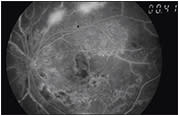

The temporal arcades and mid peripheral retina should be examined in detail to exclude PDR, including NVD (Figure 2), neovascularization elsewhere, preretinal hemorrhage, vitreous hemorrhage, or fibrovascular tissue.

Figure 2. Proliferative diabetic retinopathy with moderate neovascularization of the disk and clinically significant macular edema in a 50-year-old patient with type 1 diabetes.